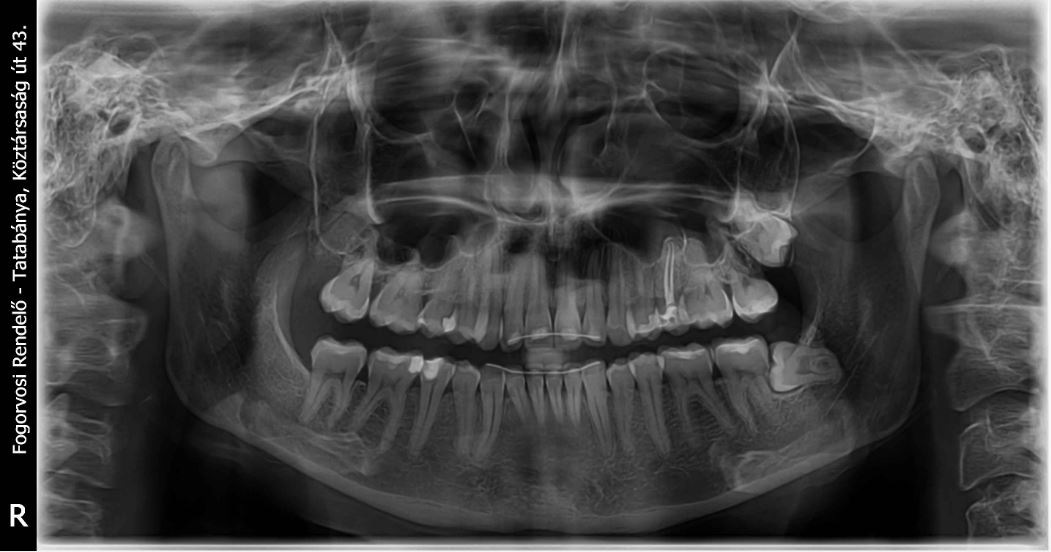

Panoráma röntgen

Digitális panoráma röntgenkészülékünkkel éles képeket tudunk készíteni, mellyel az apróbb elváltozások (szuvas léziók, gyökér körüli gyulladás) is könnyebben diagnosztizálhatók.